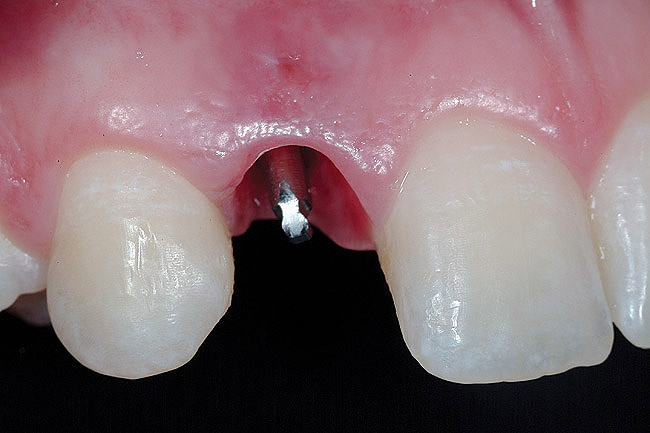

After atraumatic site preparation, two 3-mm diameter by 10-mm in length one-piece implants were seated at the No. 7 and No. 10 sites (Zimmer Dental, Carlsbad, CA) (Figure 9). Note the emergence profile formed by the esthetic recontouring of the crest of the ridge prior to implant site preparation. Confirmation of implant positioning was then verified by placing the TempStent II guide over the surgical sites (Figure 10). Ideally, because the heads of these implants are not wide and they do not lend themselves to gross preparation to reduce the facial aspect, the implants may not be suited for maxilla that has a steep angle. Minor preparation of the head can be performed facially but should be kept to a minimum.

Figure 9  Minimally invasive small-diameter implant placement.

Figure 9

Figure 10  Implant placement verification.

Figure 10